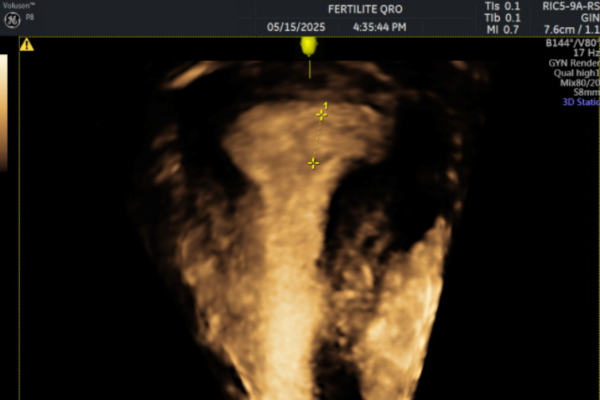

Imágenes de pólipos endometriales

- Ecografía transvaginal:

Es el primer estudio recomendado. Permite observar engrosamientos o imágenes compatibles con pólipos dentro del endometrio. Es rápida, accesible y no invasiva.